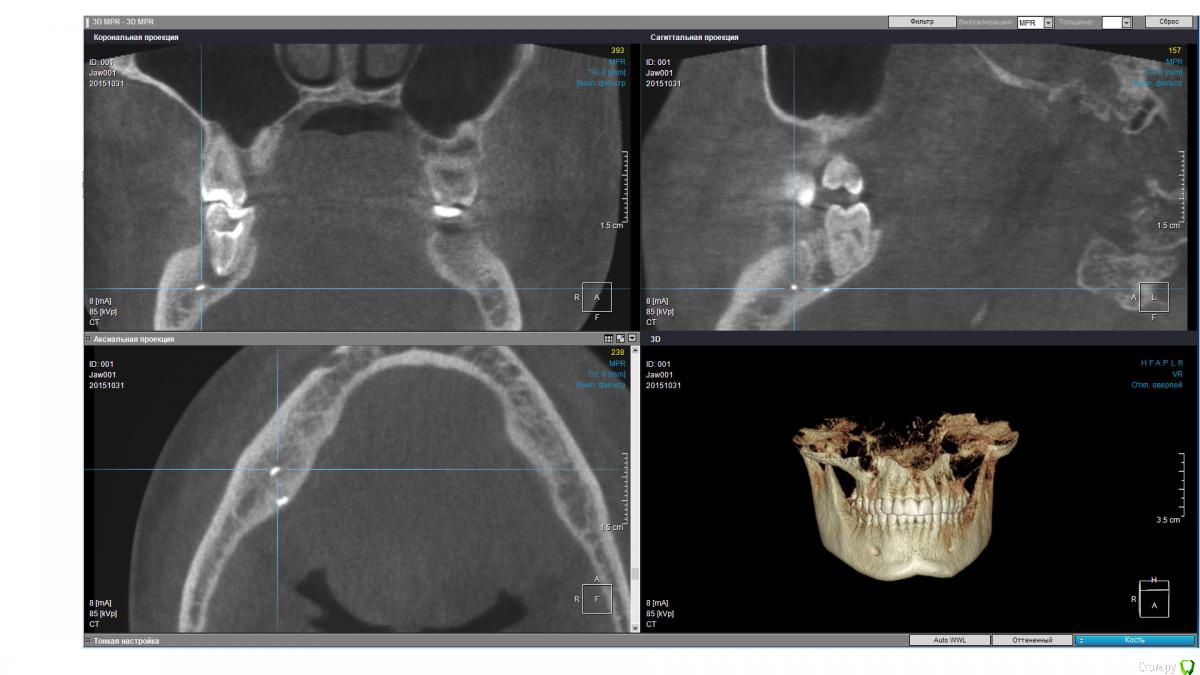

isubru Опубликовано 31 октября, 2015 Поделиться Опубликовано 31 октября, 2015 (изменено) Здравствуйте, Депульпировали зуб, потом он болел где-то с год. Больно было сильно надкусывать, потом боль прошла. "Смеркалось". Через какое-то время на десне сформировался "гноепровод". Постоянно что-то течет. Зуб предлагают удалять (должен сказать, что эта процедура настолько тут в ходу, что на неё всех поголовно отправляют). Сделал КТ. Под 47 действительно 2 кисты, но что интересно на дне полостей какие-то плотные нитевидные "обломки" в 2.5-2.8мм длинной и 1мм в диаметре. Буду очень признателен совету, как мне избавится от этой напасти. Зуб, видимо, уже не спасити?31 ноября 2015 Чуть менее годом ранее. Изменено 31 октября, 2015 пользователем isubru Ссылка на комментарий

DmitrySH Опубликовано 31 октября, 2015 Поделиться Опубликовано 31 октября, 2015 Если только на основании данного КТ, то есть шансы и спасти.На КТ фрагментов инструмента не увидел. Есть какие-то точки. Но надо понимать, что пломбировочным материал, инструменты и тп в каналах сильно "фонят" на КТ. Прицельные снимки есть? Ссылка на комментарий

isubru Опубликовано 31 октября, 2015 Автор Поделиться Опубликовано 31 октября, 2015 (изменено) Да, был. Нужно поискать. Только там в принципе тоже самое. Одна киста, что между 46 и 47 слабо различима в той проекции, хорошо видно только ту, что под другим корнем. PS. Прикрепил в 1й пост. Относительно точек, вряд ли это артефакт (только 2 специфических места на всей CT). Да и на прицельном снимке они есть. Какова вероятность, что они могли быть причиной образования кист(к примеру, механическое повреждение ими при надкусывании на этом зубе)? Изменено 31 октября, 2015 пользователем isubru Ссылка на комментарий